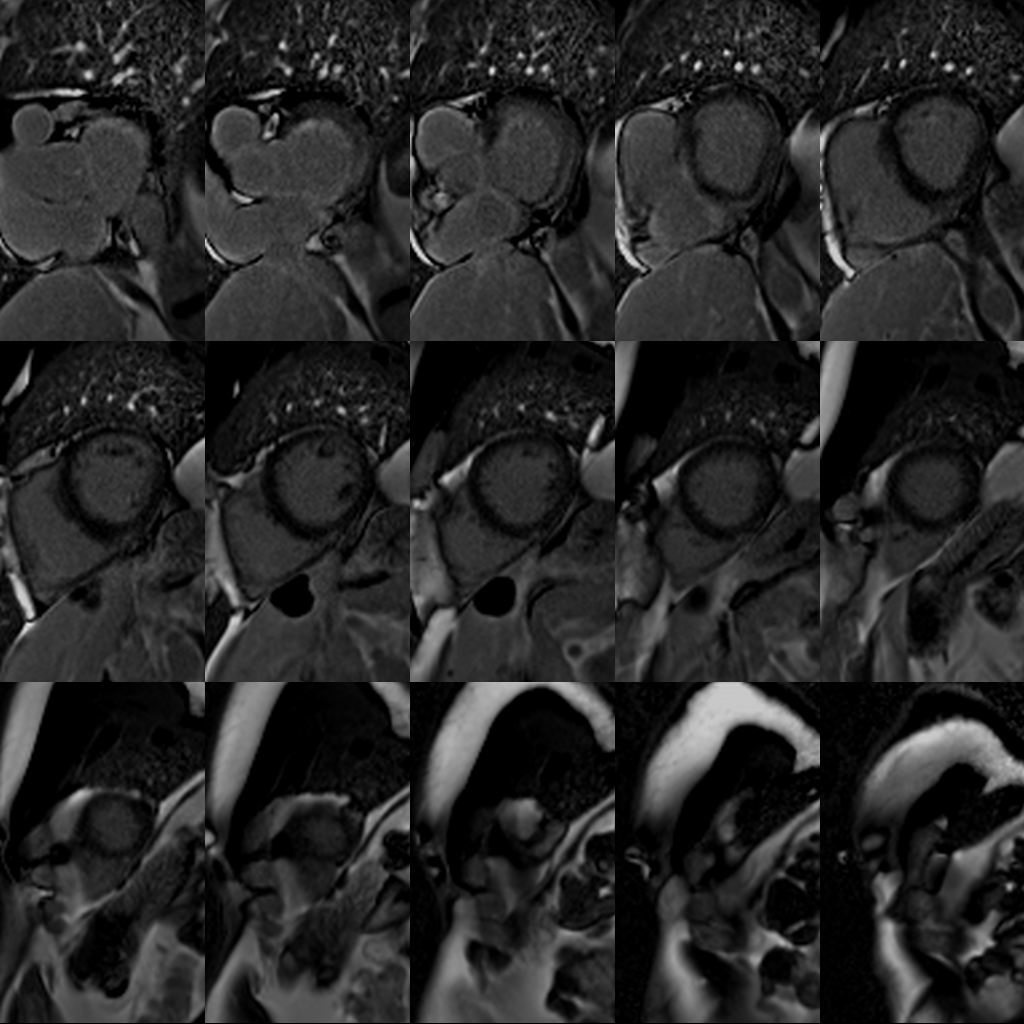

LGE